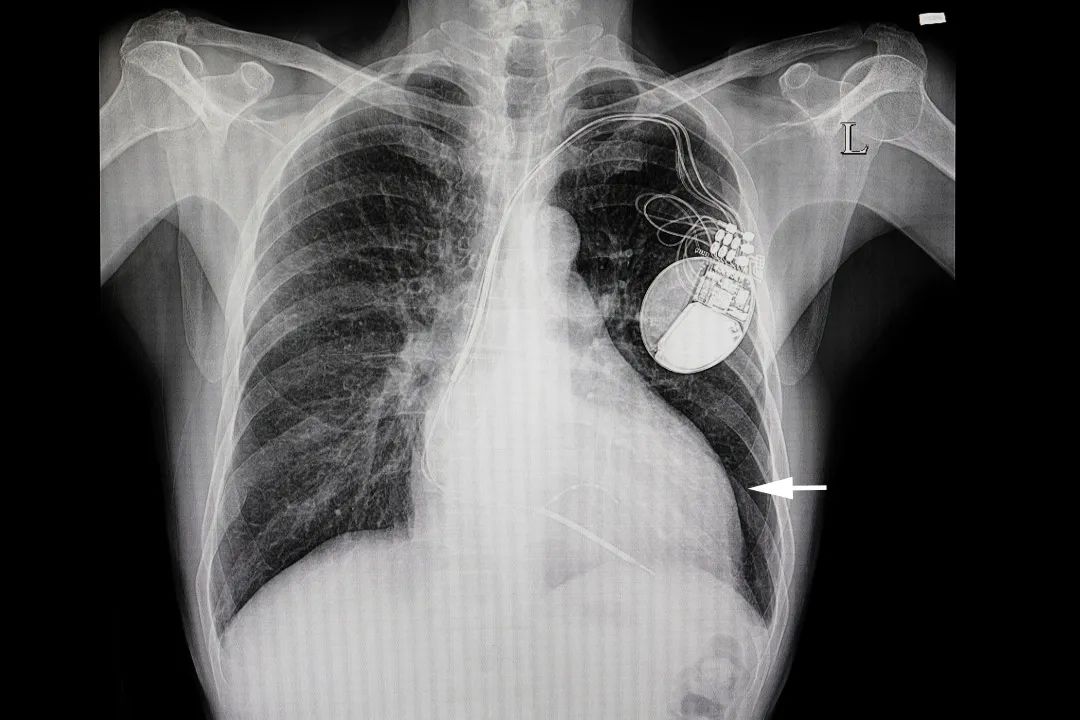

心脏起搏器是一种植入于体内的电子治疗仪器,通过脉冲发生器发放由电池提供能量的电脉冲,通过导线电极的传导,刺激电极所接触的心肌,使心脏激动和收缩,从而达到治疗由于某些心律失常所致的心脏功能障碍的目的。

大多数起搏器约为手表表盘大小,在皮下置入,植入位置因人而异,一般左右胸前都可以,目前大多是放置在左胸前,患者看不见但能摸得着。随着科技的发展,目前已有胶囊大小的无导线心脏起搏器出现,无导线起搏器被专用的输送系统送至心脏内部,患者完全感觉不到它的存在。